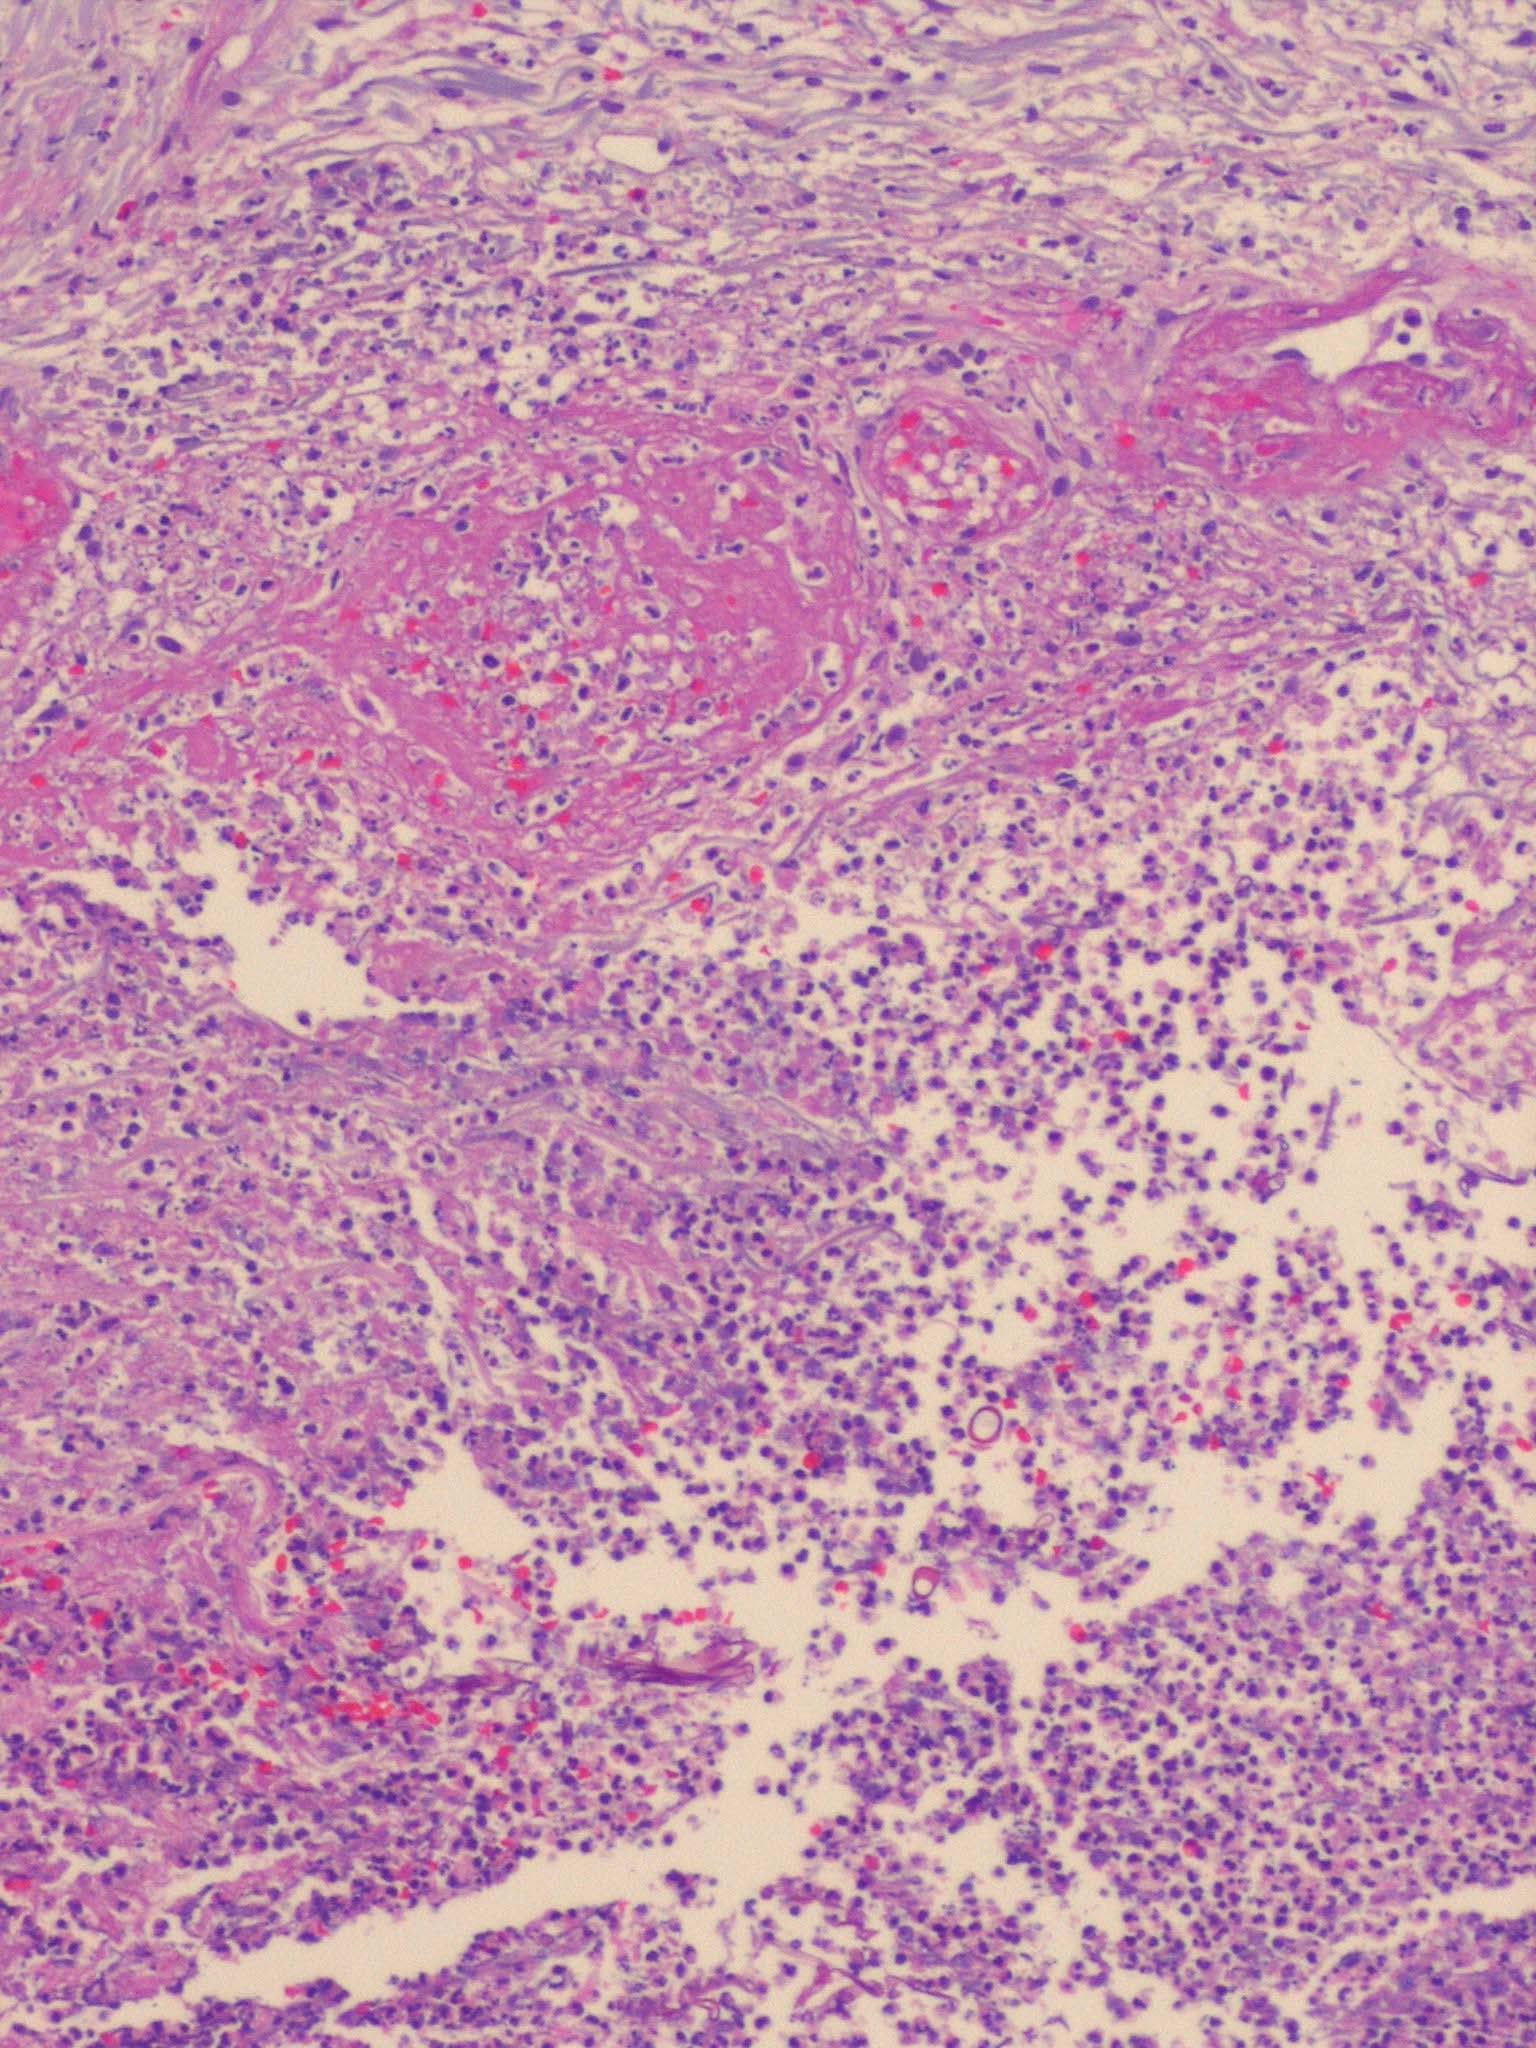

Zygomycosis =فطار عفني